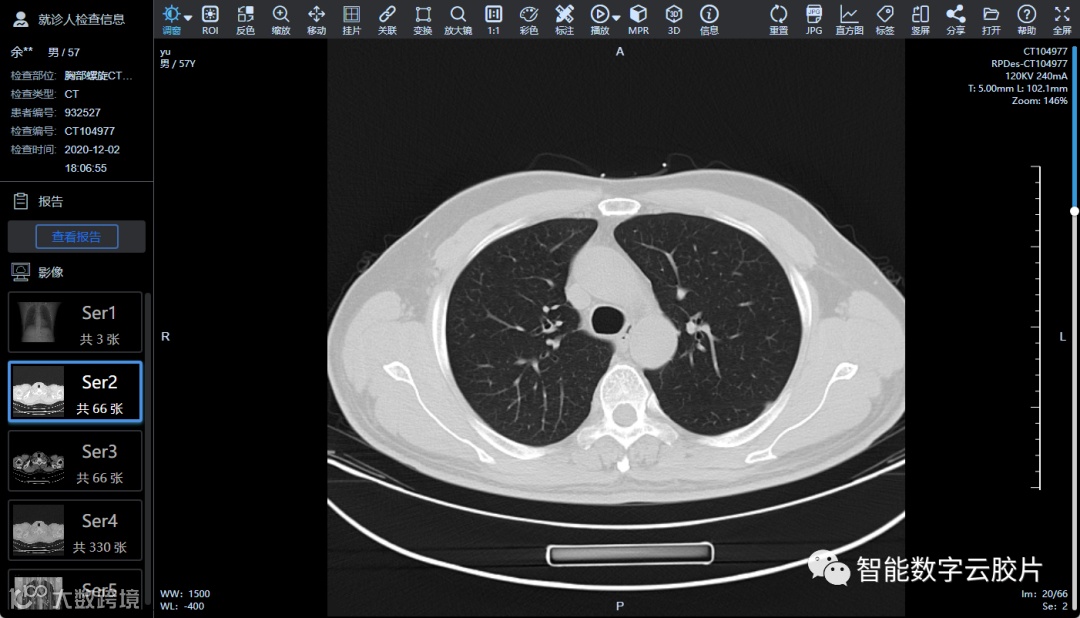

医学云影像属于高清无损的医学影像,患者做完影像检查后,系统安全加密后自动上传到专用云端平台。

检查报告完成后,患者可以通过手机、PAD或者电脑,随时随地查看和分享自己的数字医学影像,方便转诊并进行长期保存。

医生也可以通过手机,PAD和电脑查看高清原始DICOM影像,进行专业阅片,如调节窗宽窗位,局部放大,测量,MPR,容积重建等,满足移动在线阅片需求。